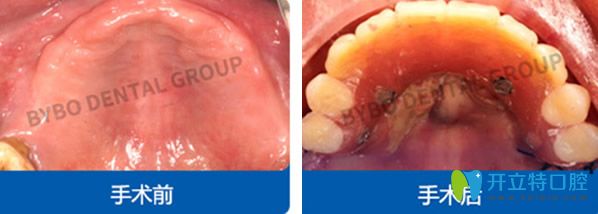

拜博口腔怎么樣?全口牙種植案例圖片賞析:

<!--<i data=20240703-sp></i>-->拜博口腔全口種植牙效果案例